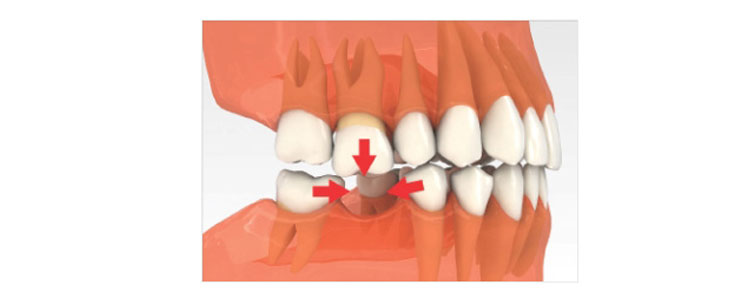

이를 뽑은 직후 인공치아 뿌리를 바로 심는 방식을 말합니다.

환자의 나이나 건강상태가 좋으며 잇몸 뼈가 임플란트에 적합하고 충분한 양과 골밀도가 있는 경우 행해지는 시술입니다.

수술 전

손상된 치아를 뽑은 당일 잇몸 주변의 염증을 제거한 후 인공치아 뿌리를 심습니다.

수술 후

인공치아 뿌리에 기둥을 연결해 미리 본을 떠 만든 임시 보철물을 장착합니다.

임플란트완성

수 개월 후 잇몸과 뼈가 모두 아물면 곧바로 임시 보철물을 떼어내고 최종 보철물을 장착하여 고정시킵니다.